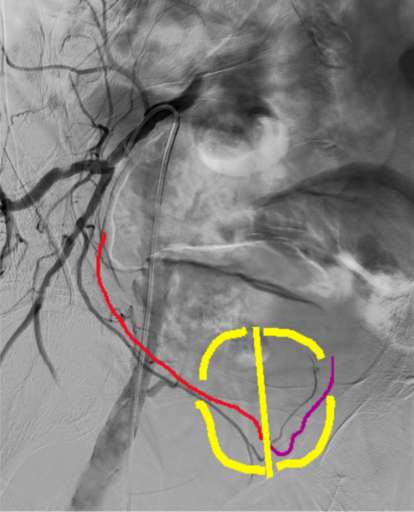

אמבוליזציה של עורק הערמונית (PAE) הוא הליך זעיר פולשני, חדשני, לא ניתוחי, המציע אלטרנטיבה לטיפולי BPH מסורתיים. הפעולה מתאימה לנפח 35 סמ"ק ומעלה ללא גבול עליון. אלו הסובלים משאריות שתן, אין מניעה לבצע את הפעולה.

הדמיה במהלך הפעולה:

במהלך הפעולה מבצעים הדמיה הנקראת: CBCT (Cone Beam CT) לצורך הערכת כלי הדם באגן, זיהוי עורקי הערמונית והעורקים הסמוכים שיש להימנע מלחסום אותם. שלב זה חשוב ביותר, מחקרים הראו שהבדיקה משפרת את סיכויי ההצלחה באופן משמעותי ומונעת חסימה של כלי דם שלא לצורך.

זיהוי וחסימת עורקי הערמונית:

לאחר זיהוי ודאי חלקיקים זעירים מוזרקים לעורקים המספקים את הערמונית, עורקים אלו מספקים את מרכז הערמונית. חסימת כלי הדם יגרום לנמק של התאים וכתוצאה מכך יגרמו לערמונית להתכווץ סביב השופכה. חשוב לדעת שאין צורך בקטטר שתן לפני או אחרי הפעולה.